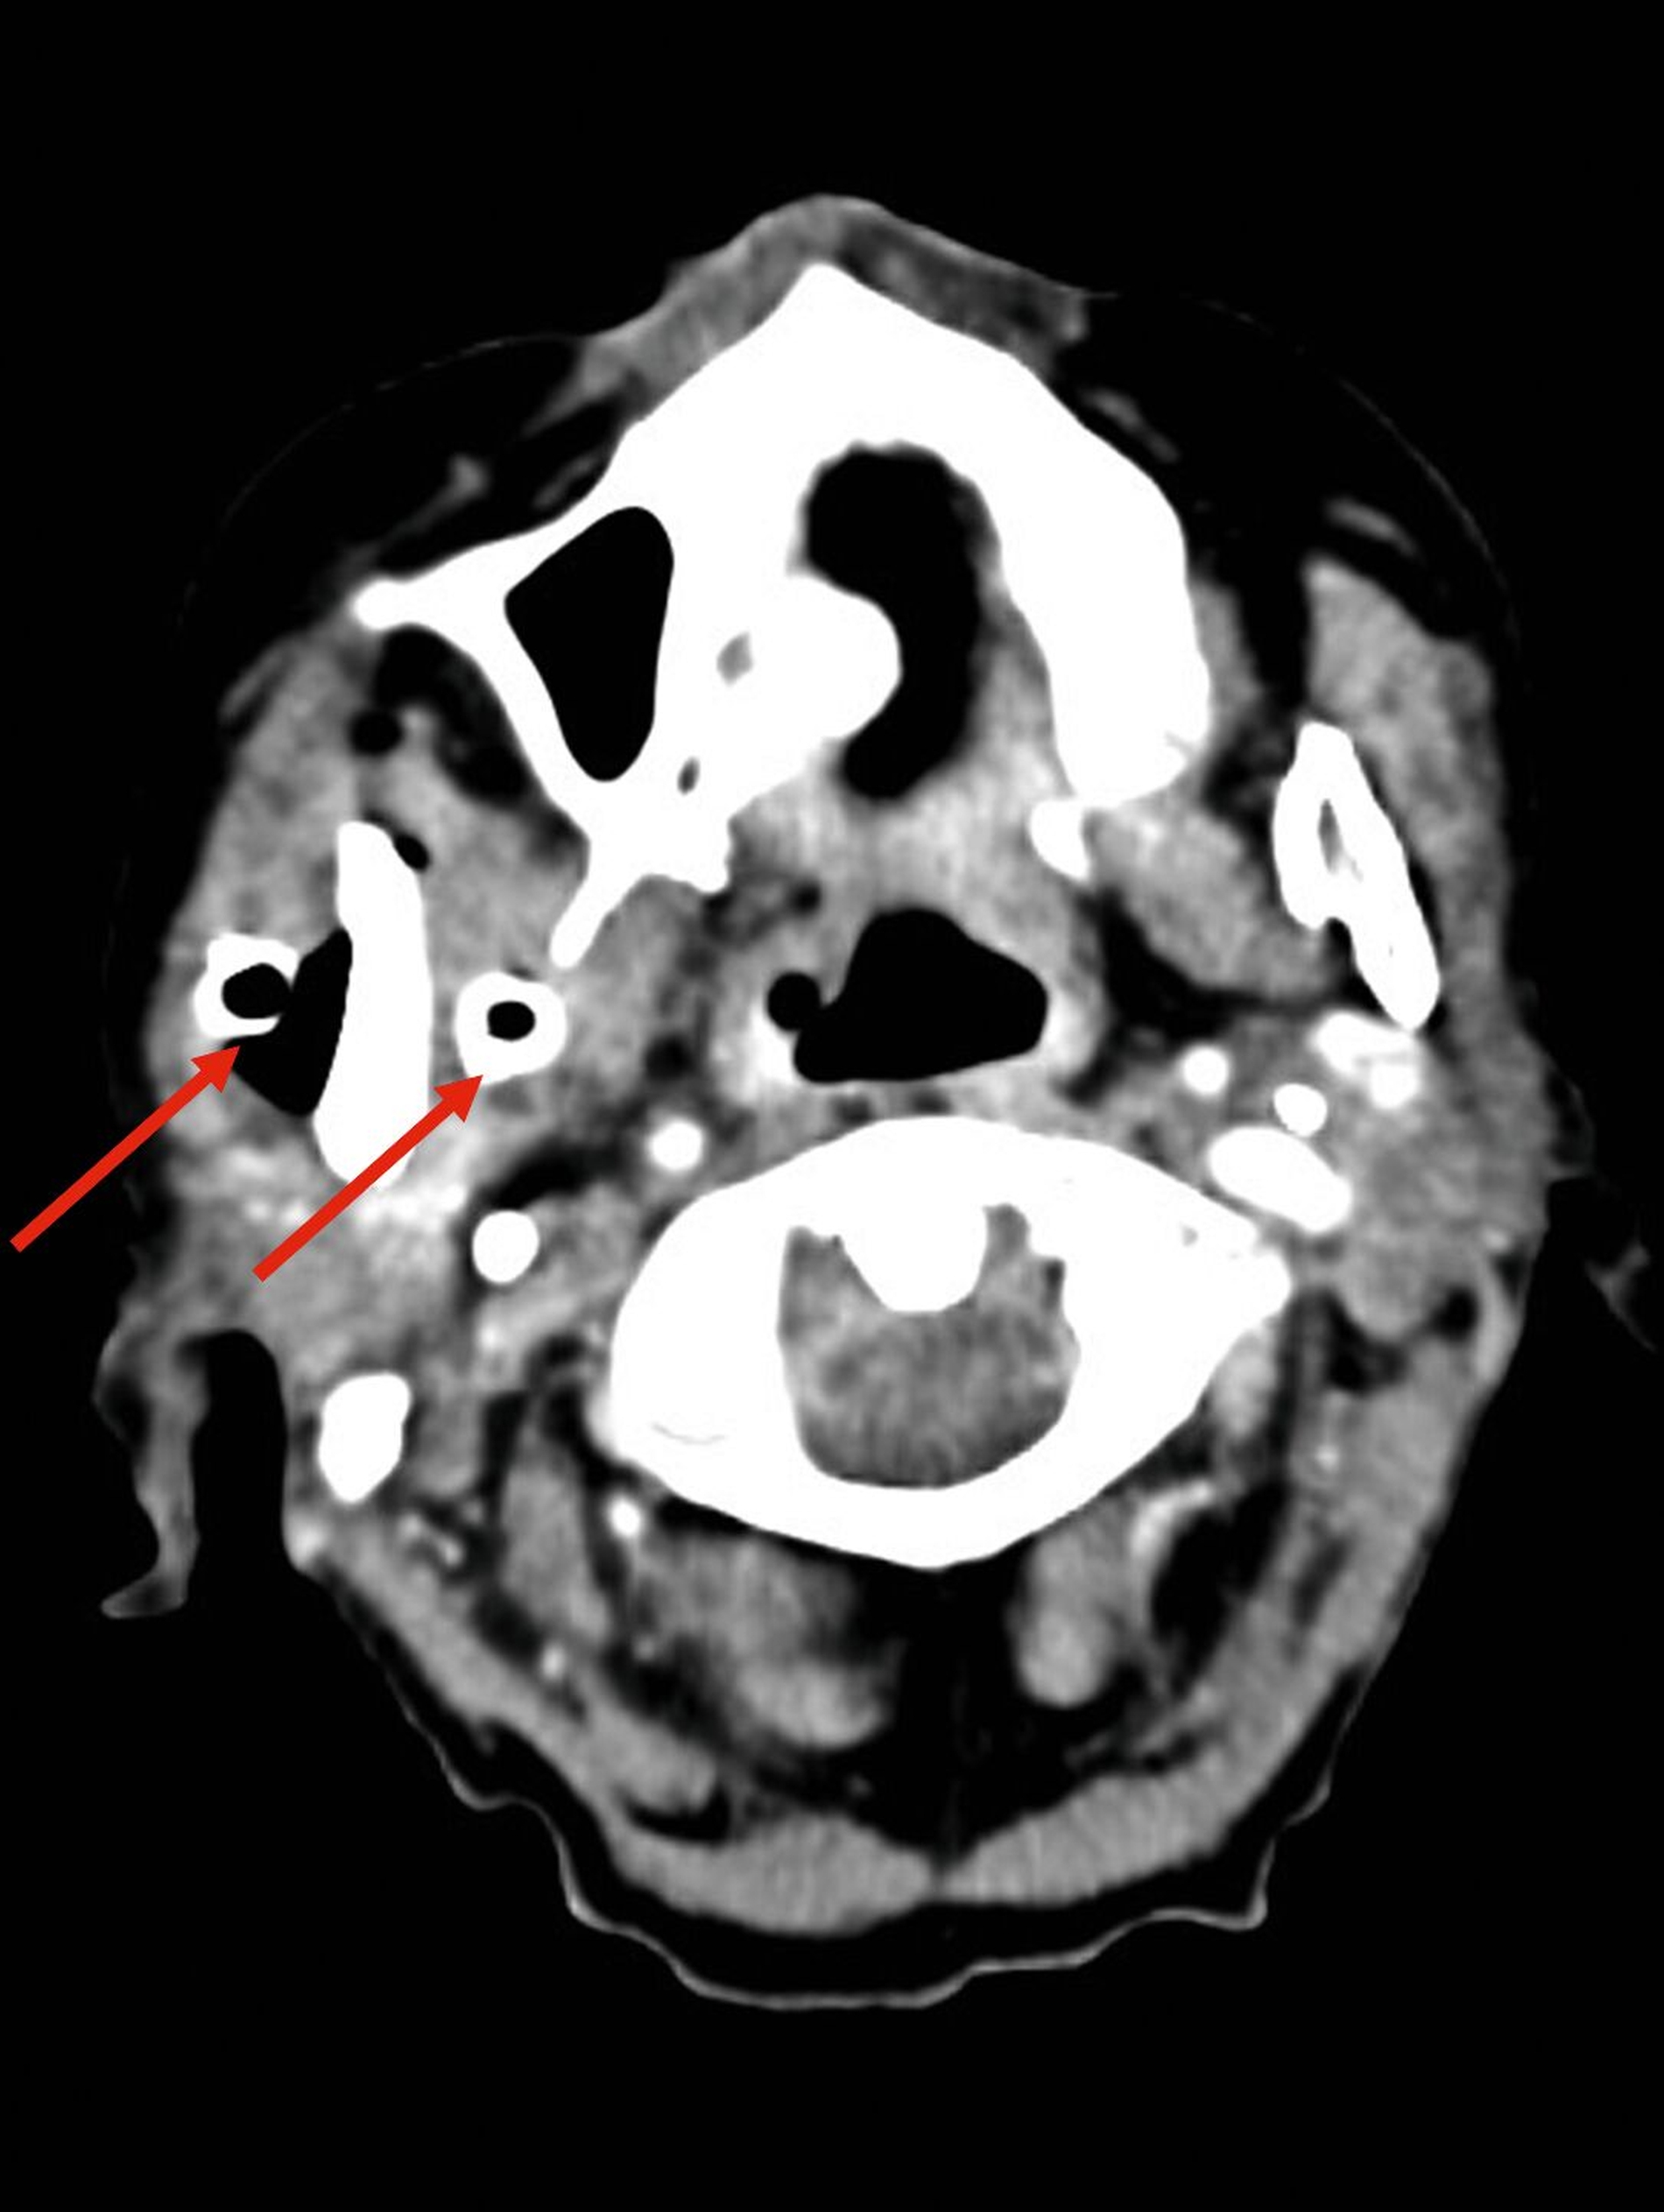

Etwa zwei Wochen nach der Entlassung wurde die Patientin mit ausgeprägter perimandibulärer Schwellung, eingeschränkter Mundöffnung, freiliegendem Knochen im rechten Unterkiefer sowie Allgemeinsymptomen wie Abgeschlagenheit und Fieber wieder stationär aufgenommen. Erneut erfolgte eine submandibuläre Inzision und Drainage in Intubationsnarkose. Die postoperative CT-Bildgebung zeigte nun eine weitgehend suffiziente Drainage der Abszesshöhlen (Abbildung 2). Mikrobiologisch zeigte sich erneut ein Streptococcus intermedius mit Clindamycin-Resistenz, ergänzt durch Enterococcus faecalis und eine anaerobe Mischflora.